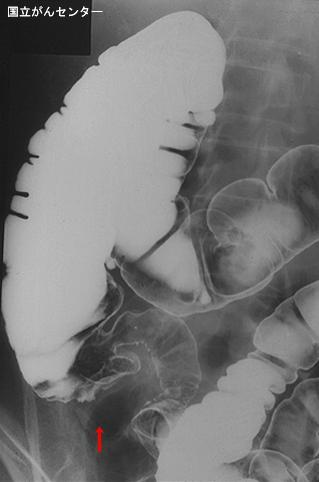

Abceso apendicular de difícil diagnóstico diferencial con tumor

[Image-ID:5653]

Enfermedad Inflamatoria - Ulcerativa/otros

colon/apéndice cecal

Rayos X

40 -